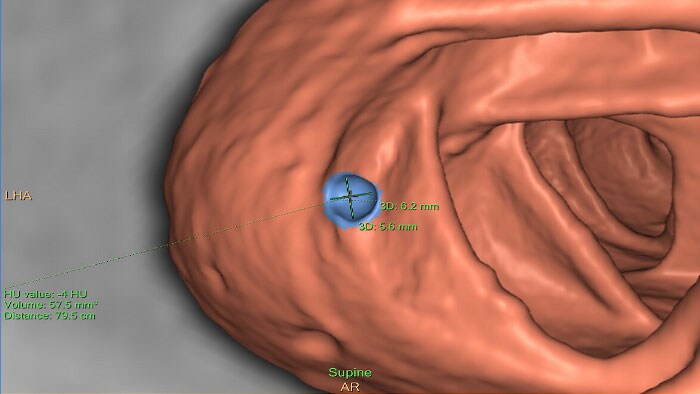

Colonoscopia virtual por TC

Permite a visualização 3D de exames ao cólon. A aplicação segmenta automaticamente o cólon preenchido com ar e apresenta uma linha central calculada.